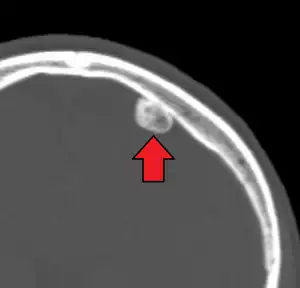

| CT scan showing an osteoma growing on inside of skull bone | |

Osteoma (plural: "osteomata" or "osteomas"), is a non-cancerous bone tumor, a type osteogenic tumor, where a new piece of bone typically grows on another piece of bone, usually on the skull and near the sinuses.[1][2] Often there are no symptoms as the tumor grows slowly, but there may be pain, headache, blocked paranasal sinuses or local swelling.[1] It may present with sinusitis.[3]

Medical imaging such as X-ray, CT scan and MRI show dense, clearly defined, round white tumors attached to bone.[1] They can be left alone if not troubling, and surgically cut out if pressure symptoms.[1] The surgery may be possible through the nose, without making a large cut.[3]

Medical imaging such as X-ray, CT scan and MRI show dense, clearly defined, round white tumors attached to bone.[1] They may be diagnosed when having medical imaging for another reason.[3] Osteomas of the paranasal sinuses and skull base can be diagnosed using CT-scan without intravenous contrast, allowing its size and relation to nearby important structures to be assessed.[3] A biopsy is not usually required.[3]